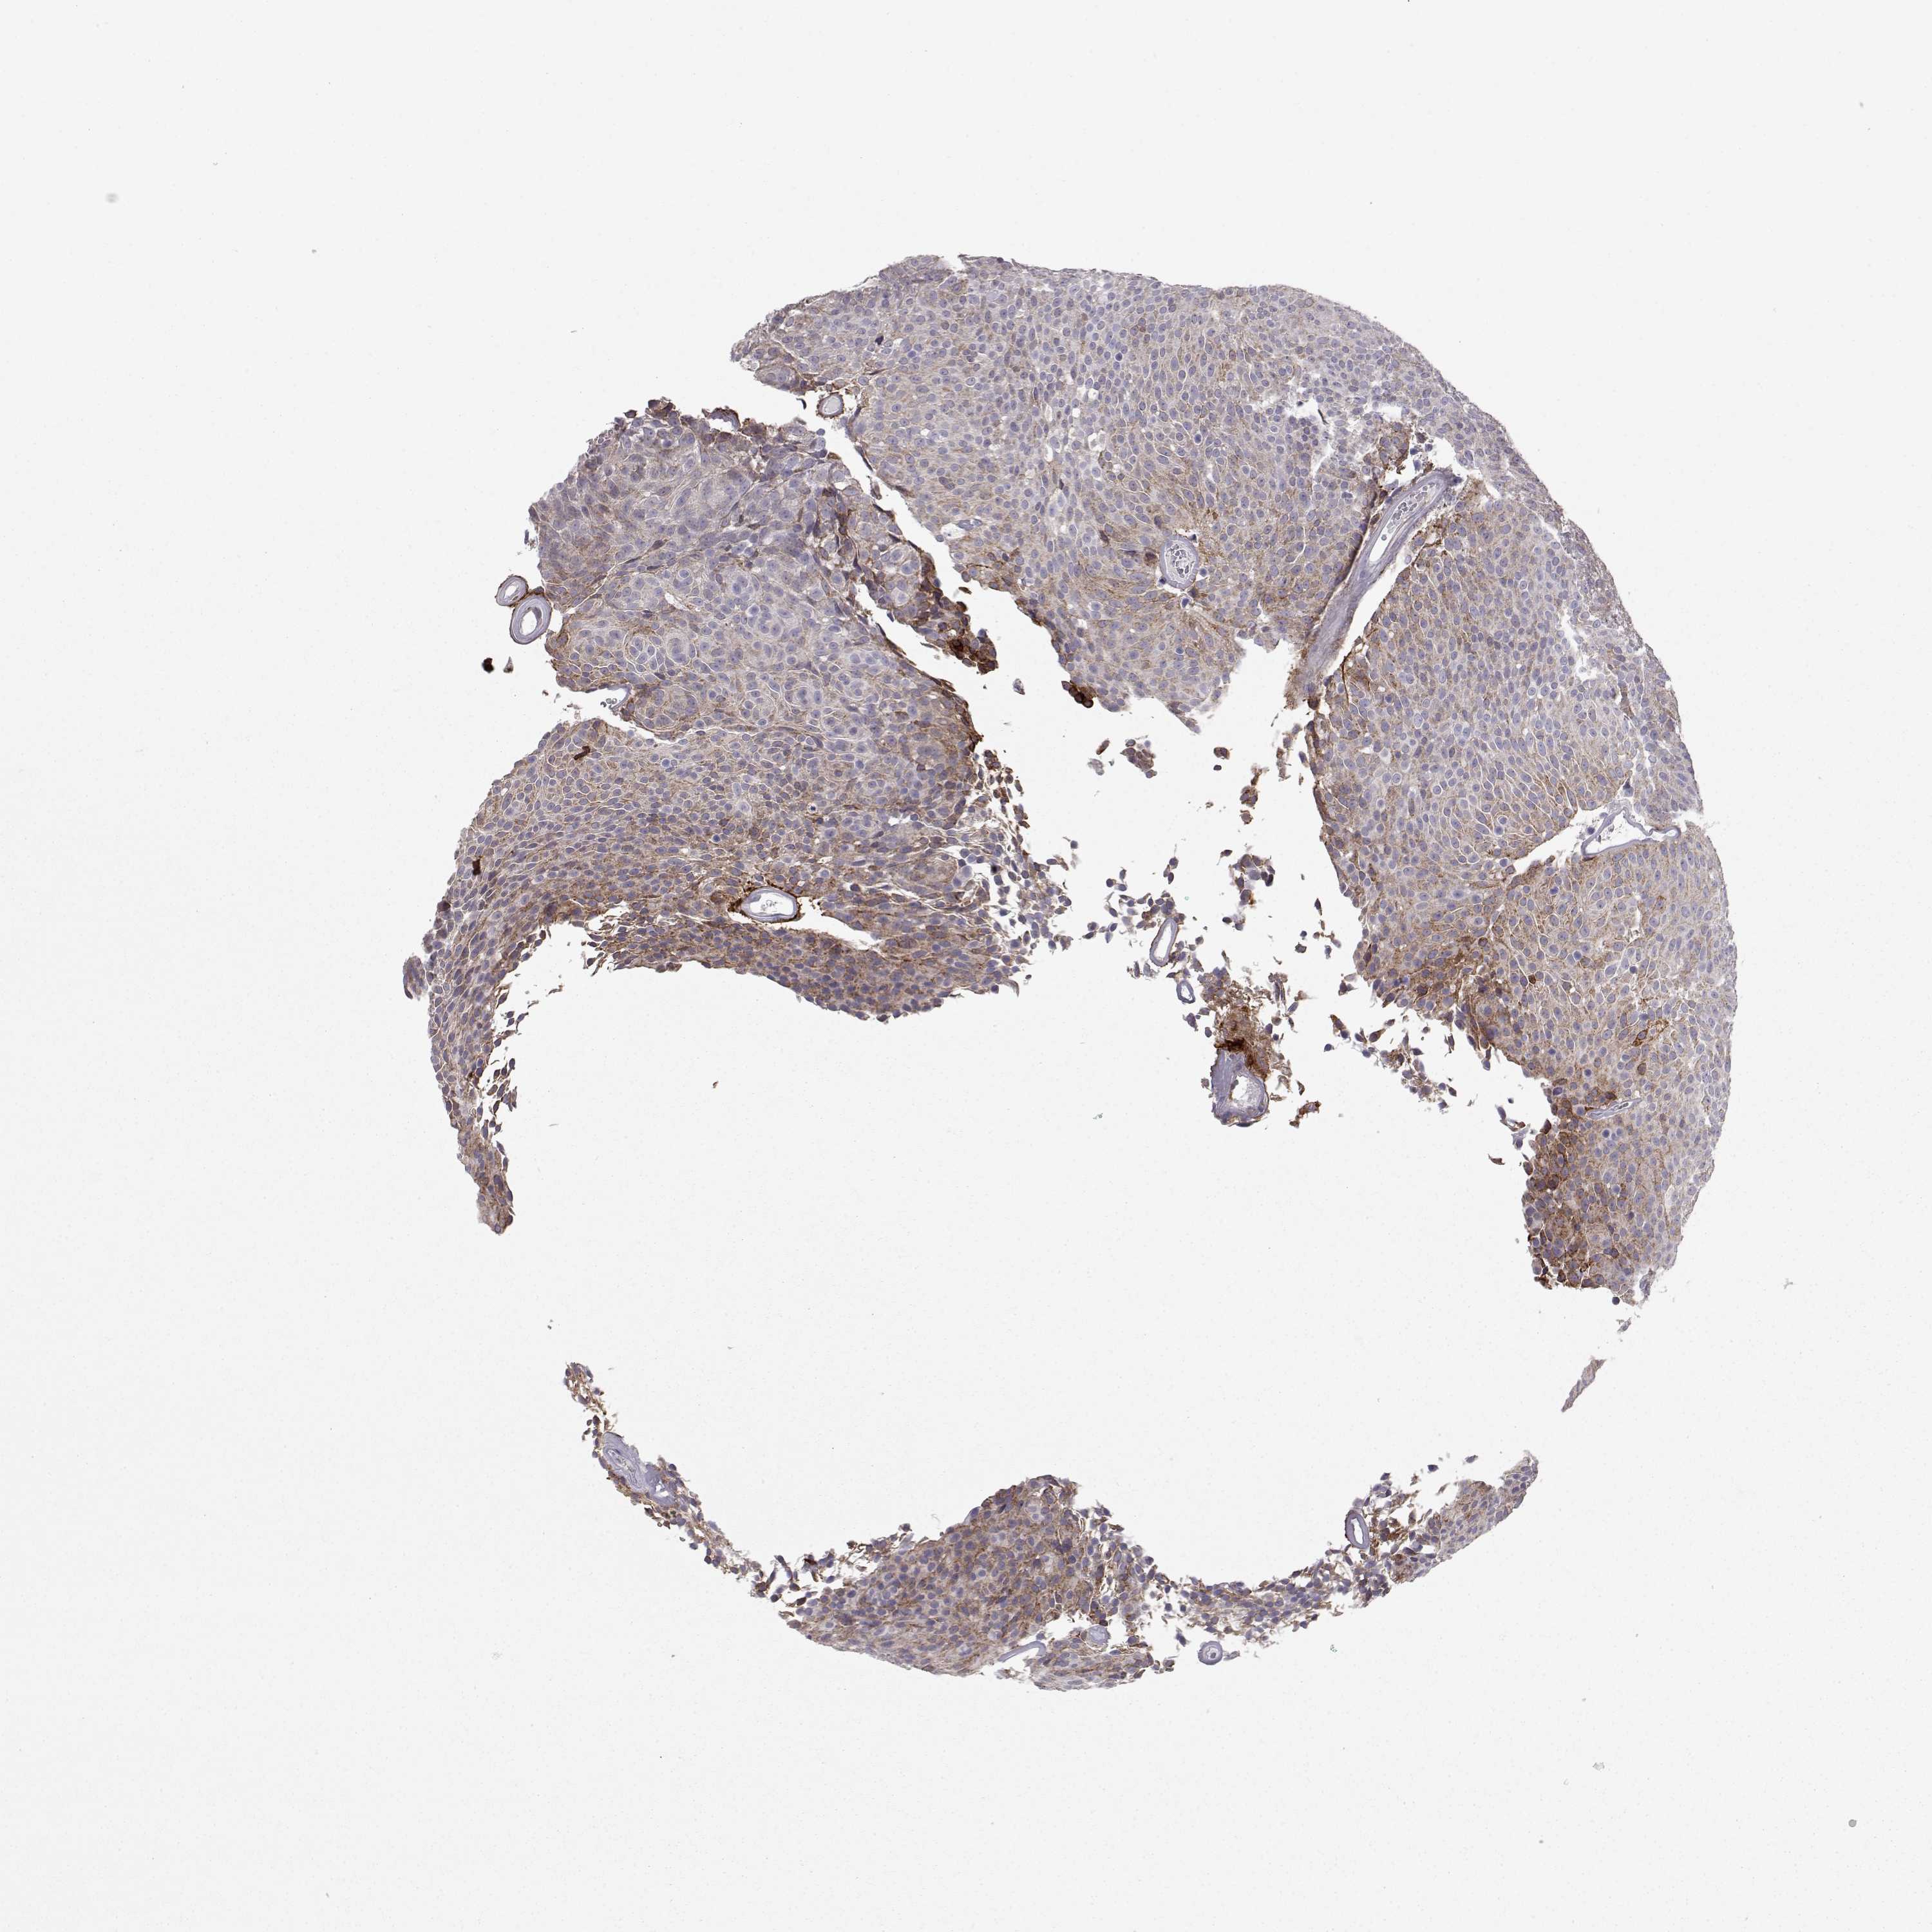

UROTHELIAL CANCER - Protein expressioni

A mouse-over function shows sample information and annotation data. Click on an image to view it in a full screen mode. Samples can be filtered based on level of antibody staining by selecting one or several of the following categories: high, medium, low and not detected. The assay and annotation is described here.

Note that samples used for immunohistochemistry by the Human Protein Atlas do not correspond to samples in the TCGA dataset.

Antibody stainingi

Antibody staining in the annotated cell types in the current human tissue is reported as not detected, low, medium, or high, based on conventional immunohistochemistry profiling in selected tissues. This score is based on the combination of the staining intensity and fraction of stained cells.

Each image is clickable and will lead to virtual microscopy that enables deeper exploration of all samples and also displays staining intensity scores, fraction scores and subcellular localization as well as patient and tissue information for each sample.

Antibody HPA008069

Antibody CAB078183

Staining

High

Medium

Low

Not detected

Intensity

Strong

Moderate

Weak

Negative

Quantity

>75%

75%-25%

<25%

None

Location

Nuclear

Cytoplasmic/membranous

Cytoplasmic/membranous,nuclear

Urothelial carcinoma, Low grade

Urothelial carcinoma, High grade

Urothelial carcinoma, NOS